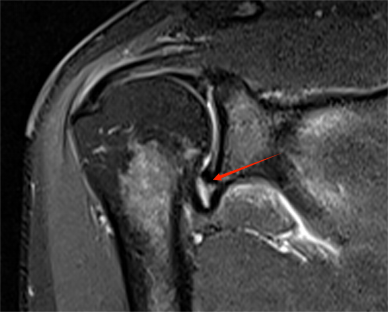

△ 游泳之后诱发髋关节滑囊炎